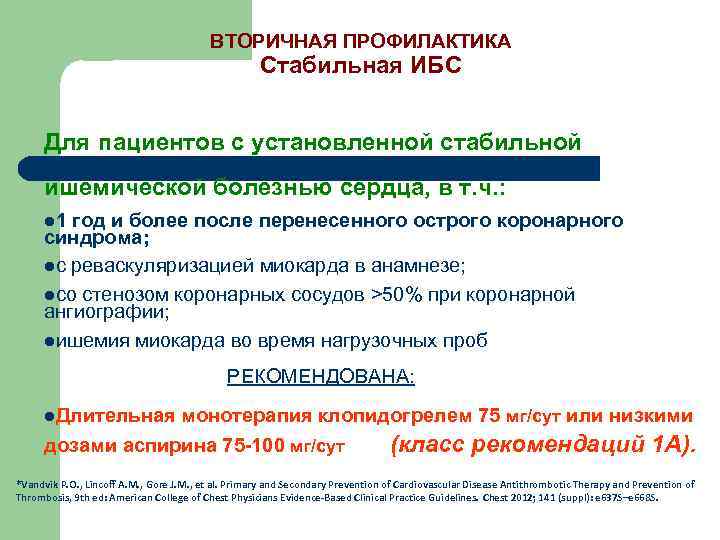

ВТОРИЧНАЯ ПРОФИЛАКТИКА Стабильная ИБС Для пациентов с установленной стабильной ишемической болезнью сердца, в т. ч. : l 1 год и более после перенесенного острого коронарного синдрома; lс реваскуляризацией миокарда в анамнезе; lсо стенозом коронарных сосудов >50% при коронарной ангиографии; lишемия миокарда во время нагрузочных проб РЕКОМЕНДОВАНА: l. Длительная монотерапия клопидогрелем 75 мг/сут или низкими дозами аспирина 75 -100 мг/сут (класс рекомендаций 1 А). *Vandvik P. O. , Lincoff A. M. , Gore J. M. , et al. Primary and Secondary Prevention of Cardiovascular Disease Antithrombotic Therapy and Prevention of Thrombosis, 9 th ed: American College of Chest Physicians Evidence-Based Clinical Practice Guidelines. Chest 2012; 141 (suppl): e 637 S–e 668 S.